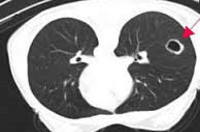

Q33.0 Врожденная киста легкого